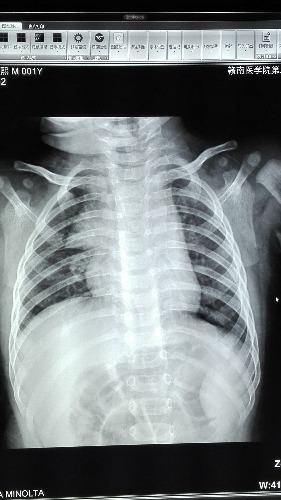

2岁,咳嗽咳痰数天,卧位胸片,胸腺有问题吗

第一例正常胸腺

第二例考虑小儿胸腺肥大。

考虑小儿胸腺肥大。